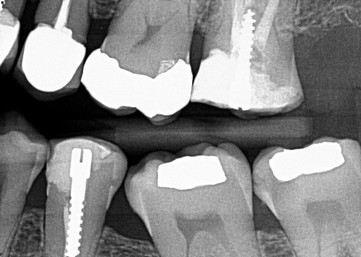

2. (Select ONE OR MORE correct answers)

The radiograph shows evidence of